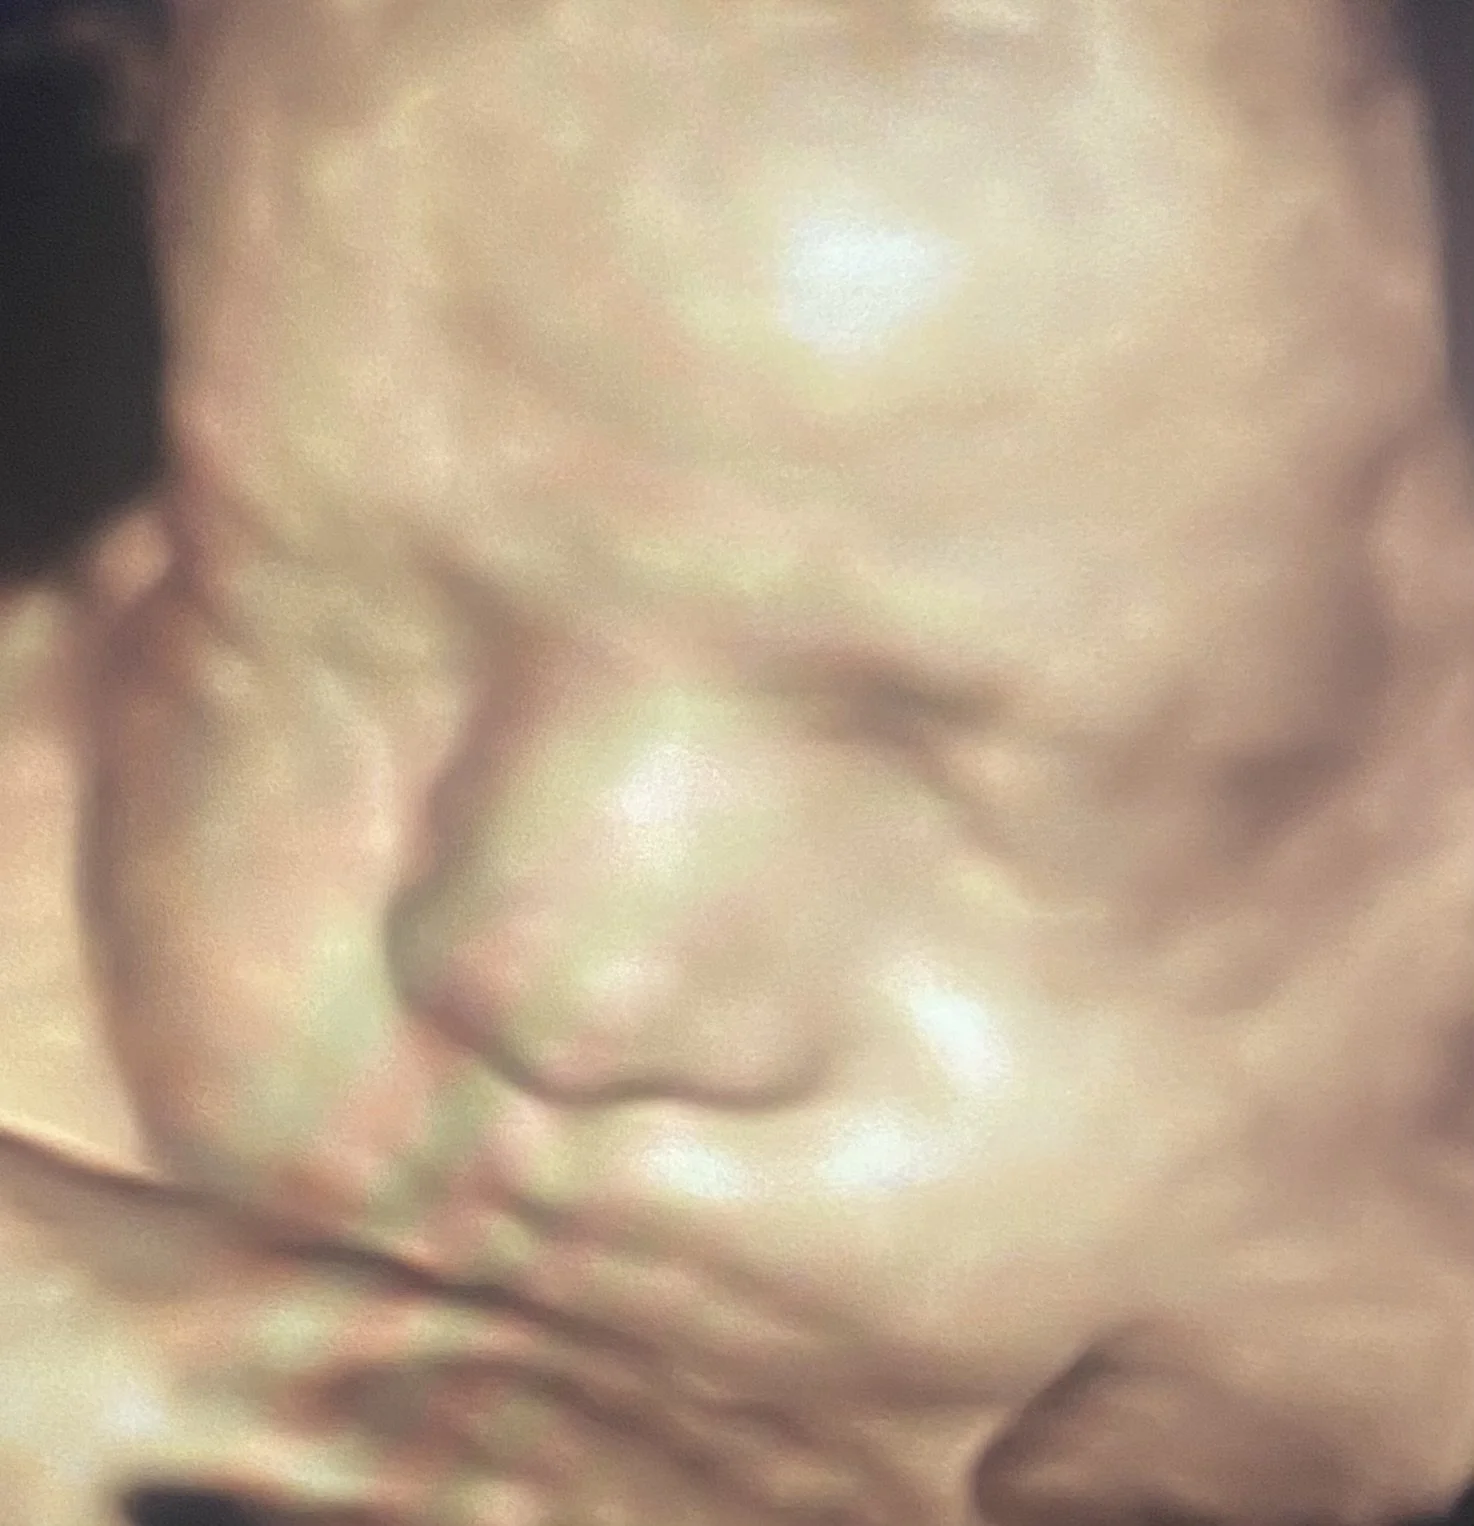

ScanSanctuary Client Scan Examples